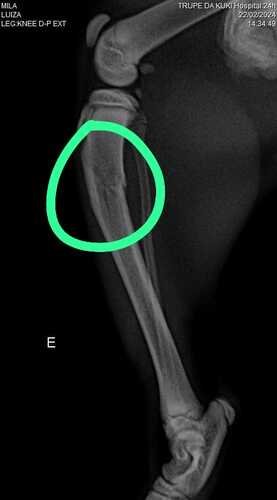

Oii pessoal, meu nome é Mila e eu tenho só 4 mesinhos. Esta noite resolvi testar se eu conseguia voar e acabei caindo do 4 andar. Mamãe quase morreu do coração, mas tá tudo bem. Tive uma fratura na minha patinha e vou precisar de uma cirurgia, infelizmente mamãe não tem como pagar tudo sozinha e eu vim pedir a ajuda de vocês. Muito obrigada 🩷